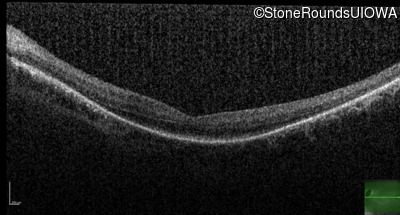

Optical Coherence Tomography - Right - 20/63 -1

Exemplar / OCT Stack

OCT Stack